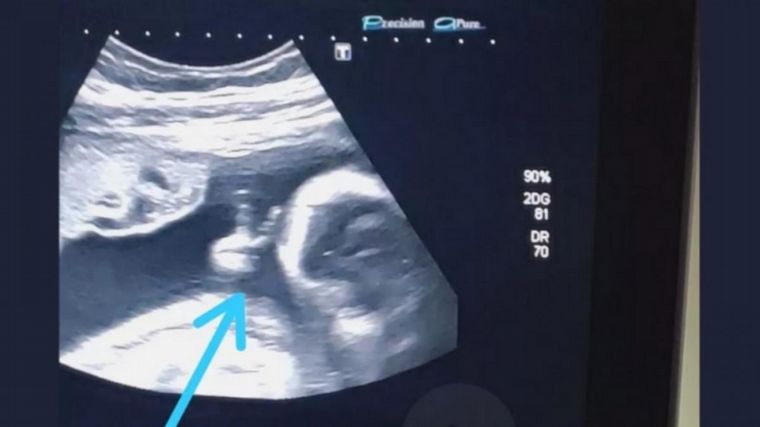

Una ecografía mostró a un bebé haciendo la "V"

Los padres del pequeño vincularon el hecho con la palabra "victoria". Creen que se trata de un mensaje de aliento de su hijo desde la panza para su papá, diagnosticado con un tumor maligno.

Felipe Moreira dos Santos, de 32 años, quien es el padre del pequeño, tomó el gesto de su hijo registrado en la ecografía como una "señal divina" en símbolo de aliento ante su delicado estado de salud.

Incluso el médico dijo: 'mira, hizo el pequeño signo de la victoria con la mano'. No lo podía creer

Mirá la imagen